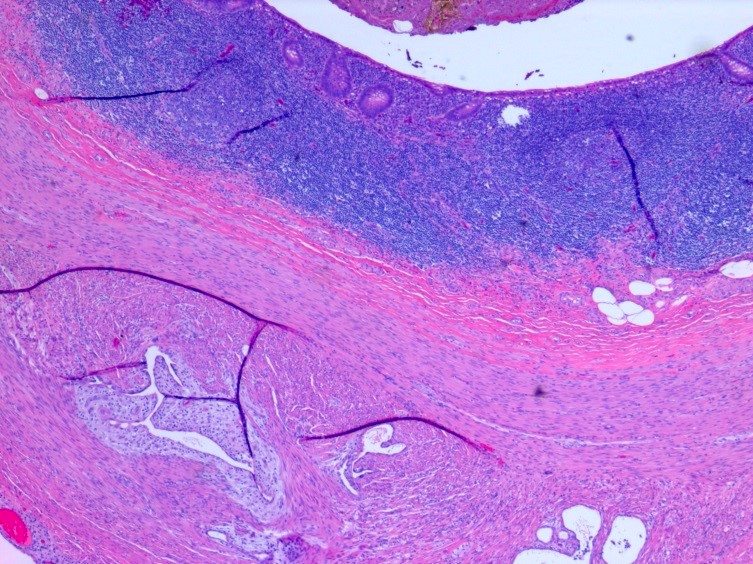

Microscopic (histologic) images

Microscopic (histologic) description

- At least 2 of the following 3 features

- Endometrial type glands

- Müllerian type epithelium (can be atrophic to cycling endometrium)

- Can show degenerative atypia (enlarged smudgy nuclei) or metaplasia

- Endometrial type stroma

- Often contains fine capillary network

- May undergo smooth muscle metaplasia, fibrosis (longstanding), decidual change

- May be myxoid (particularly in pregnancy)

- Stroma may be the only identifiable component (stromal endometriosis)

- Evidence of chronic hemorrhage (hemosiderin laden or foamy macrophages)

- Endometrial type glands